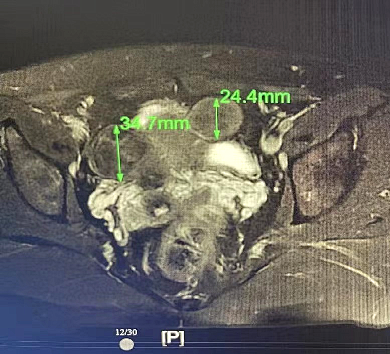

*前                          *后

还能从图像信息中提取出成像区域的温度信号实现对消融手术的实时温度监控这大大提高了*的*性和有效性